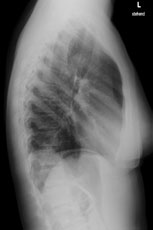

Eine 36-jährige Patientin kommt zu Ihnen in die Praxis. Sie berichtet über einen grippalen, fieberhaften Infekt, seit einer Woche bestehend.

In der Lungenauskultation sind Rasselgeräusche beidseits basal zu hören. Bei einem CRP von 160 mg/l veranlassen Sie ein Thoraxröntgen mit der Frage nach Infiltrat.

Hier sehen Sie die Bilder:

Thorax seitlich